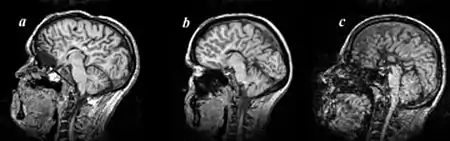

Agenesis of the corpus callosum (ACC) is a rare birth defect in which there is a complete or partial absence of the corpus callosum. It occurs when the development of the corpus callosum, the band of white matter connecting the two hemispheres in the brain, in the embryo is disrupted. The result of this is that the fibers that would otherwise form the corpus callosum are instead longitudinally oriented along the ipsilateral ventricular wall and form structures called Probst bundles.

Callosal disorders can be diagnosed through brain imaging studies or during autopsy.[6] They may be diagnosed through an MRI, CT scan, Sonography, prenatal ultrasound, or prenatal MRI.[1]